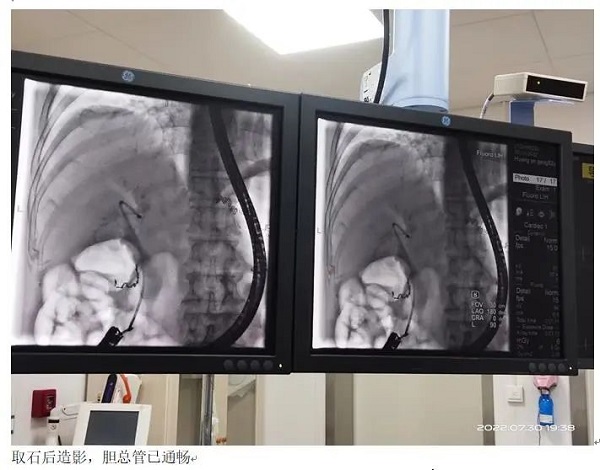

7月30日,外二科团队与介入室医生、护理和麻醉师齐心协作,成功为该患者开展了ERCP+EST术。术后患者恢复顺利,未出现并发症,目前已痊愈出院。